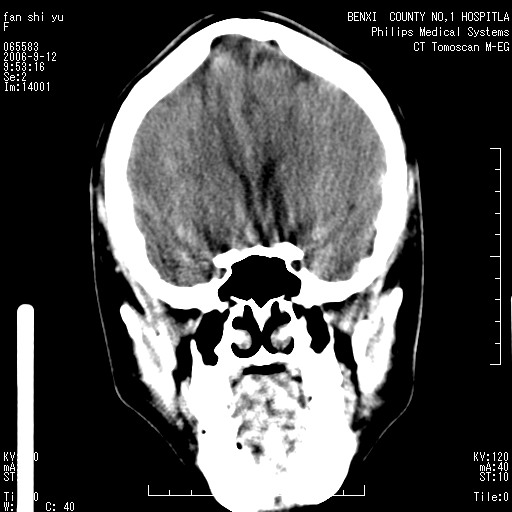

标题: CT4607:看看这个头颅冠状位。

女,22岁,自觉头顶部质硬包块.

巨大蛛网膜粒压迹。

巨大蛛网膜粒压迹